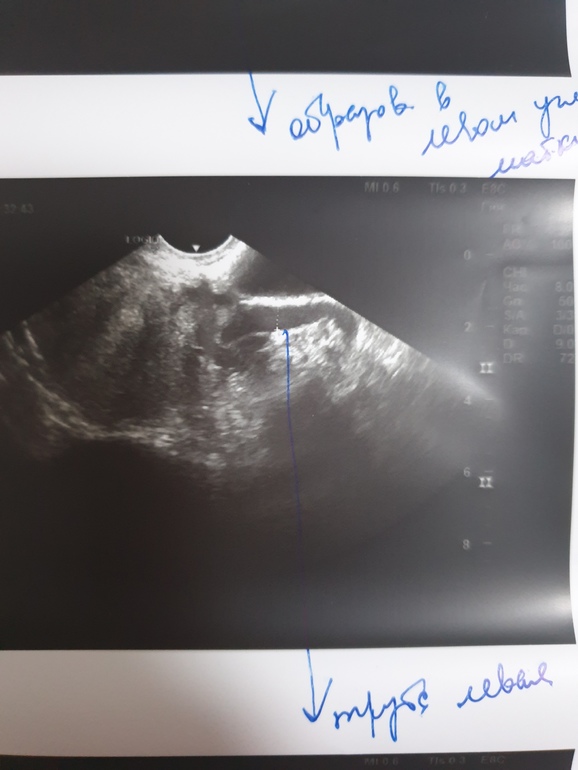

И результаты прошлого узи (с прошлого цикла)

ФолликулометрияДевочки, вчера сходила на УЗИ на 19д.ц. сначала все было прекрасно, ЖТ есть 20мм, говорит хорошее, Эндик пышный, 13мм, и все бы ничего, но вдруг она разглядела у меня расширенную трубу слева, на 7мм, и сказала, либо это внематочная, либо гидросальпингс. Я в шоке, понимаю что ничего хорошего из этого не выйдет, ее слова звучали как приговор. Больше она мне ничего не сказала, отправила сдать на хгч и на различные инфекции. Лечения пока тоже никакого не назначила. Ну конечно же мой воспаленый мозг полез в интернет читать различные статьи и делать выводы, мол сколько мне жить осталось😁 и решила сравнить с результатами узи прошлого цикла на 17дц. В заключении было написано что у меня слева расширенные вены до *внимание, 7мм! И тут у меня появилась надежда, а может врач просто перепутала мою расширенную вену с трубой, и ничего страшного там нет? Раньше мне подобных диагнозов типа гидросальпингс и прочих проблем с трубами не ставили. Подскажите пожалуйста, может ли доктор перепутать на узи два этих диагноза?